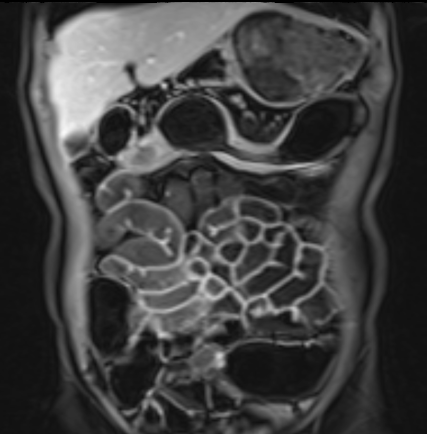

Bệnh nhân nữ 48 tuổi, đang điều trị bằng thuốc kháng TNF, được chỉ định nội soi đại tràng.

Phát hiện hẹp lòng ruột ở đại tràng sigma, không thể vượt qua được khi nội soi.

MR-enterography được thực hiện để đánh giá mức độ lan rộng của chỗ hẹp.

Ruột non bình thường, nhưng ghi nhận các đoạn hẹp ở đại tràng xuống và đại tràng ngang.

Cả hai đoạn hẹp đều có thành ruột dày đến 8 mm và ngấm thuốc rõ rệt theo kiểu niêm mạc ở đại tràng xuống và kiểu phân lớp ở đại tràng ngang.

Giãn ruột trước chỗ hẹp được ghi nhận ở cả hai đoạn.

Do các chỗ hẹp này không hiện diện khi nội soi đại tràng trước khi điều trị kháng TNF, nhiều khả năng chúng đã hình thành trong quá trình điều trị.

Do đó, quyết định phẫu thuật cắt đại tràng gần toàn bộ với miệng nối hồi-sigma đã được đưa ra.